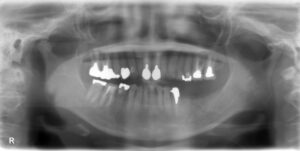

下顎大臼歯1本欠損症例

BEFORE AFTER 26歳女性/下1本欠損/インプラント埋込手術 【治療内容】 右下第二大臼歯は神経の処置をした後…